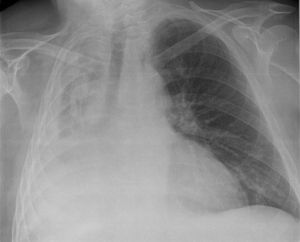

the collapse or closure of a lung resulting in reduced or absent gas exchange. It may affect part or all of a lung. It is usually unilateral. It is a condition where the alveoli are deflated down to little or no volume, as distinct from pulmonary consolidation, in which they are filled with liquid. 1.atelectasis 2.bronchectasis. ??

Which type of atelectasis is this? Compression ,resorption or fibrosis?